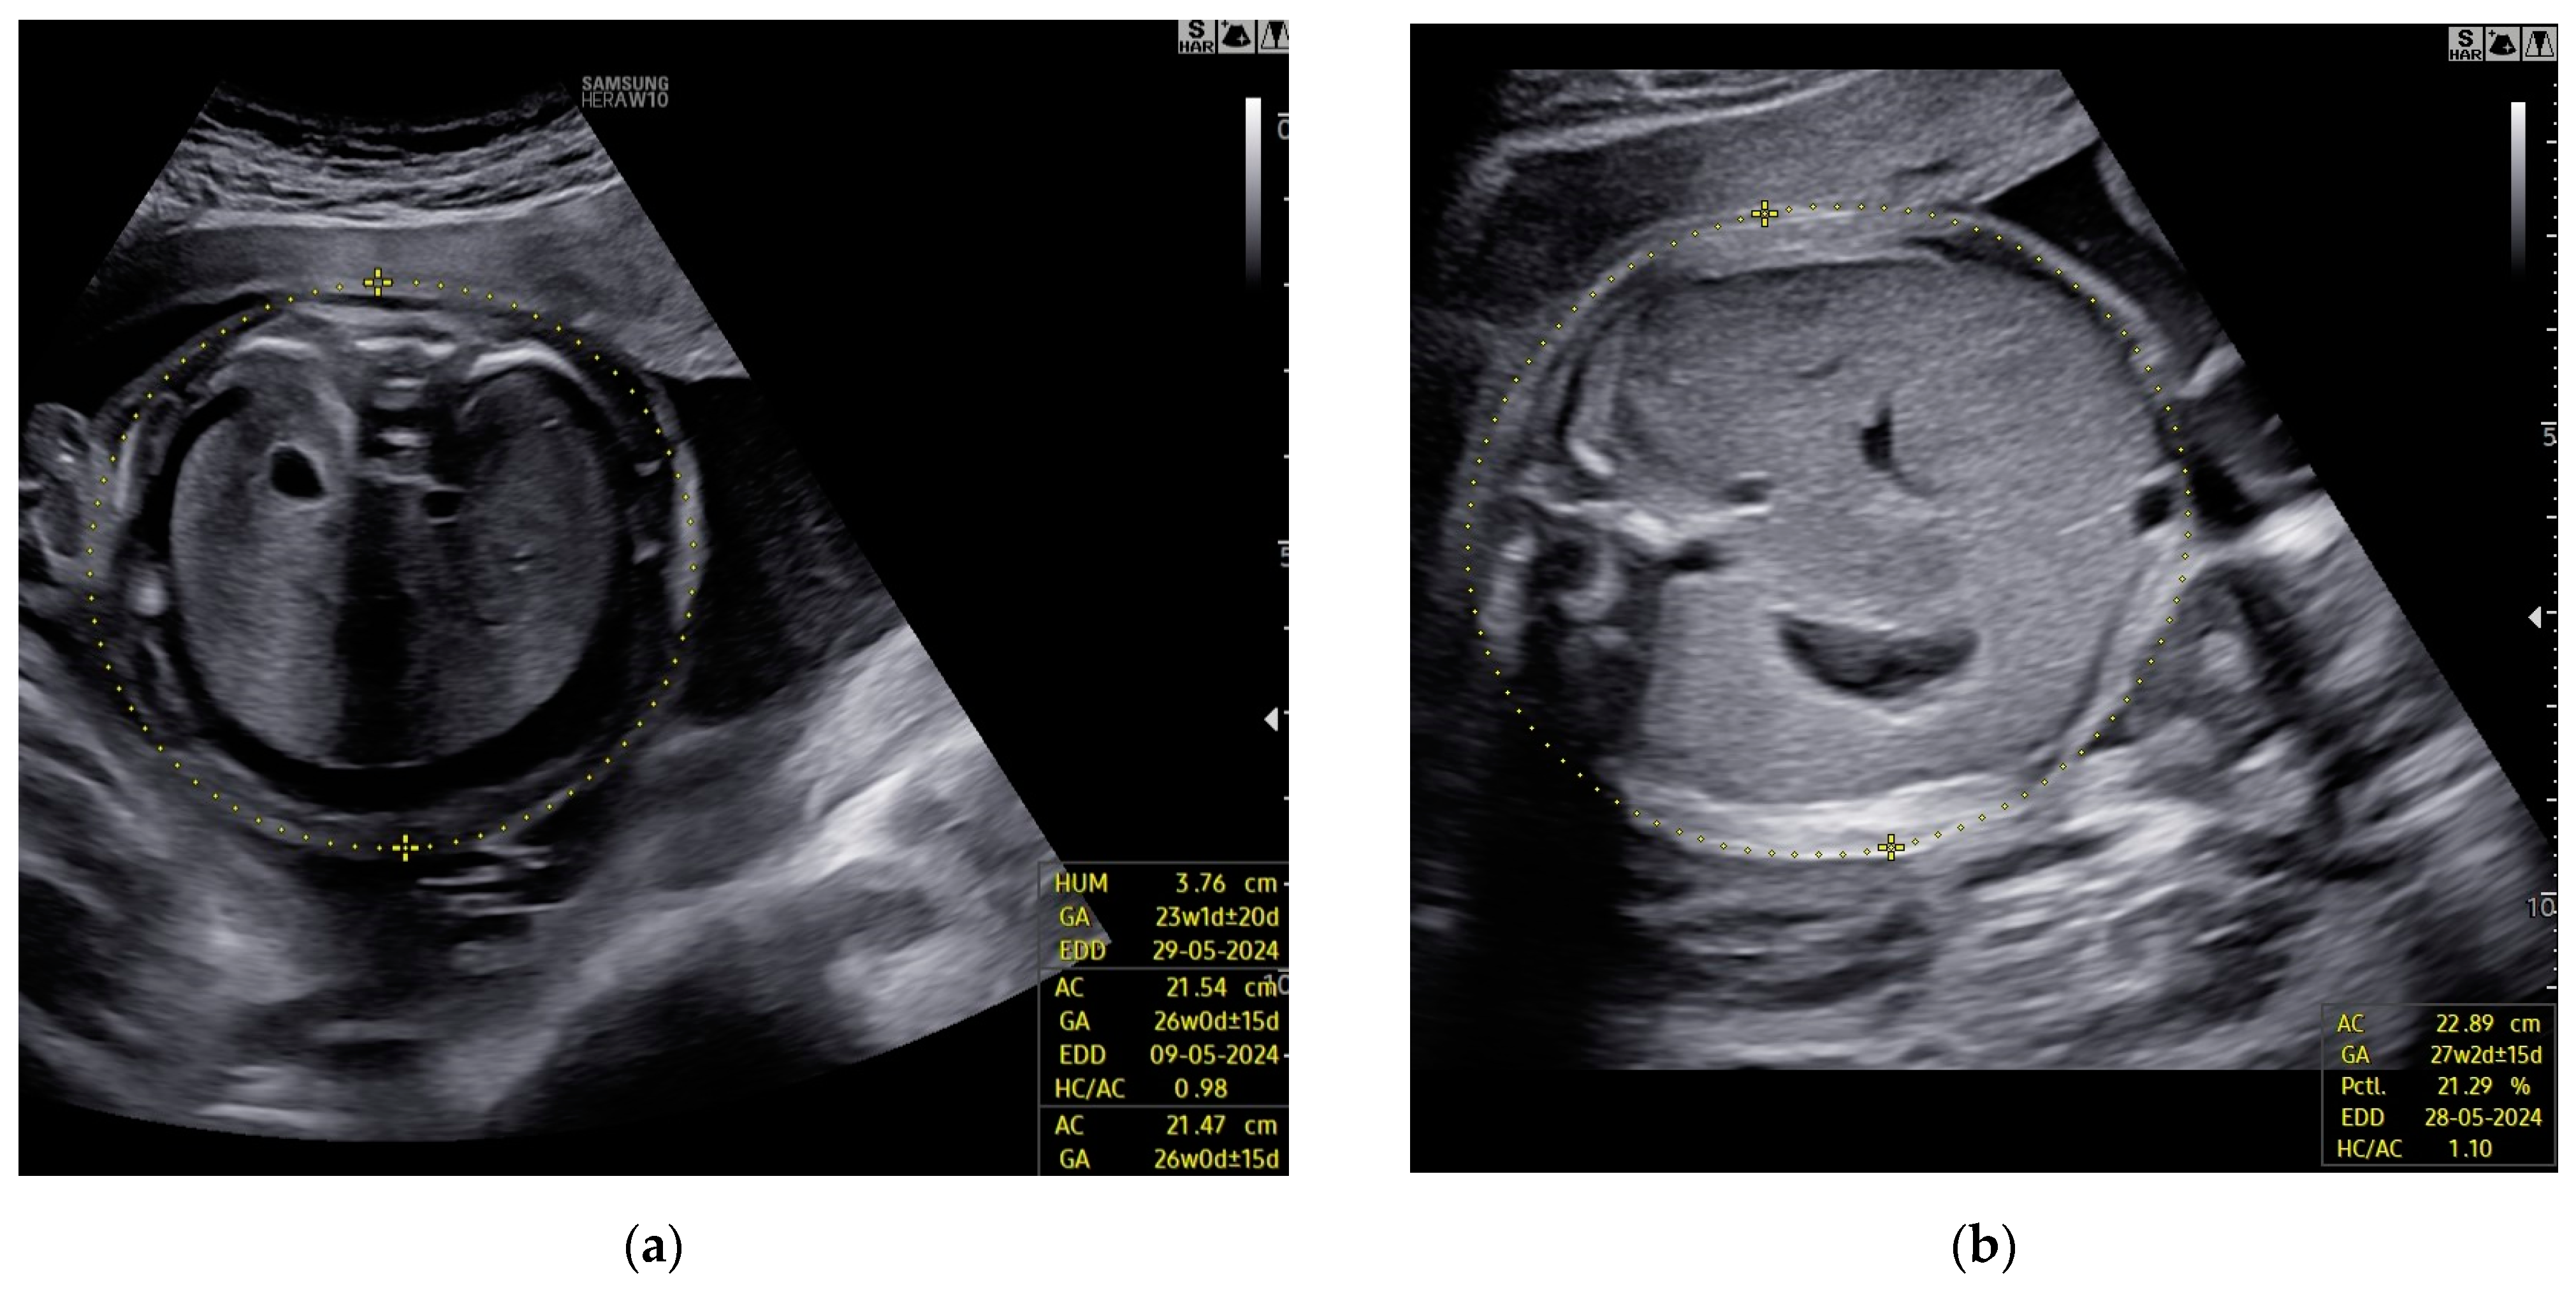

A 29-year-old woman, in the 21st week of her second pregnancy, was referred to the hospital due to anomalies detected during the anatomy scan—specifically, fetal hydrops accompanied by ascites and pericardial effusion (Figure 7a).

Three weeks after the last intrauterine transfusion, the patient underwent a follow-up ultrasound examination, revealing almost complete resolution of fetal hydrops, with only a small amount of fluid remaining in the pericardium. Fetal echocardiography detected mitral valve regurgitation (Figure 7b). The PSV of the MCA measured 47.57 cm/s (1.37 MoM), which was within normal limits. The estimated fetal weight was 920 g, appropriate for the gestational age.

Figure 7. Case 7: Abnormalities in the fetal heart ultrasound: (a) pericardial effusion before the first intrauterine transfusion, 21 weeks of gestation; (b) regurgitation of the mitral valve and total resolution of pericardial effusion, 2 weeks after the second intrauterine transfusion.